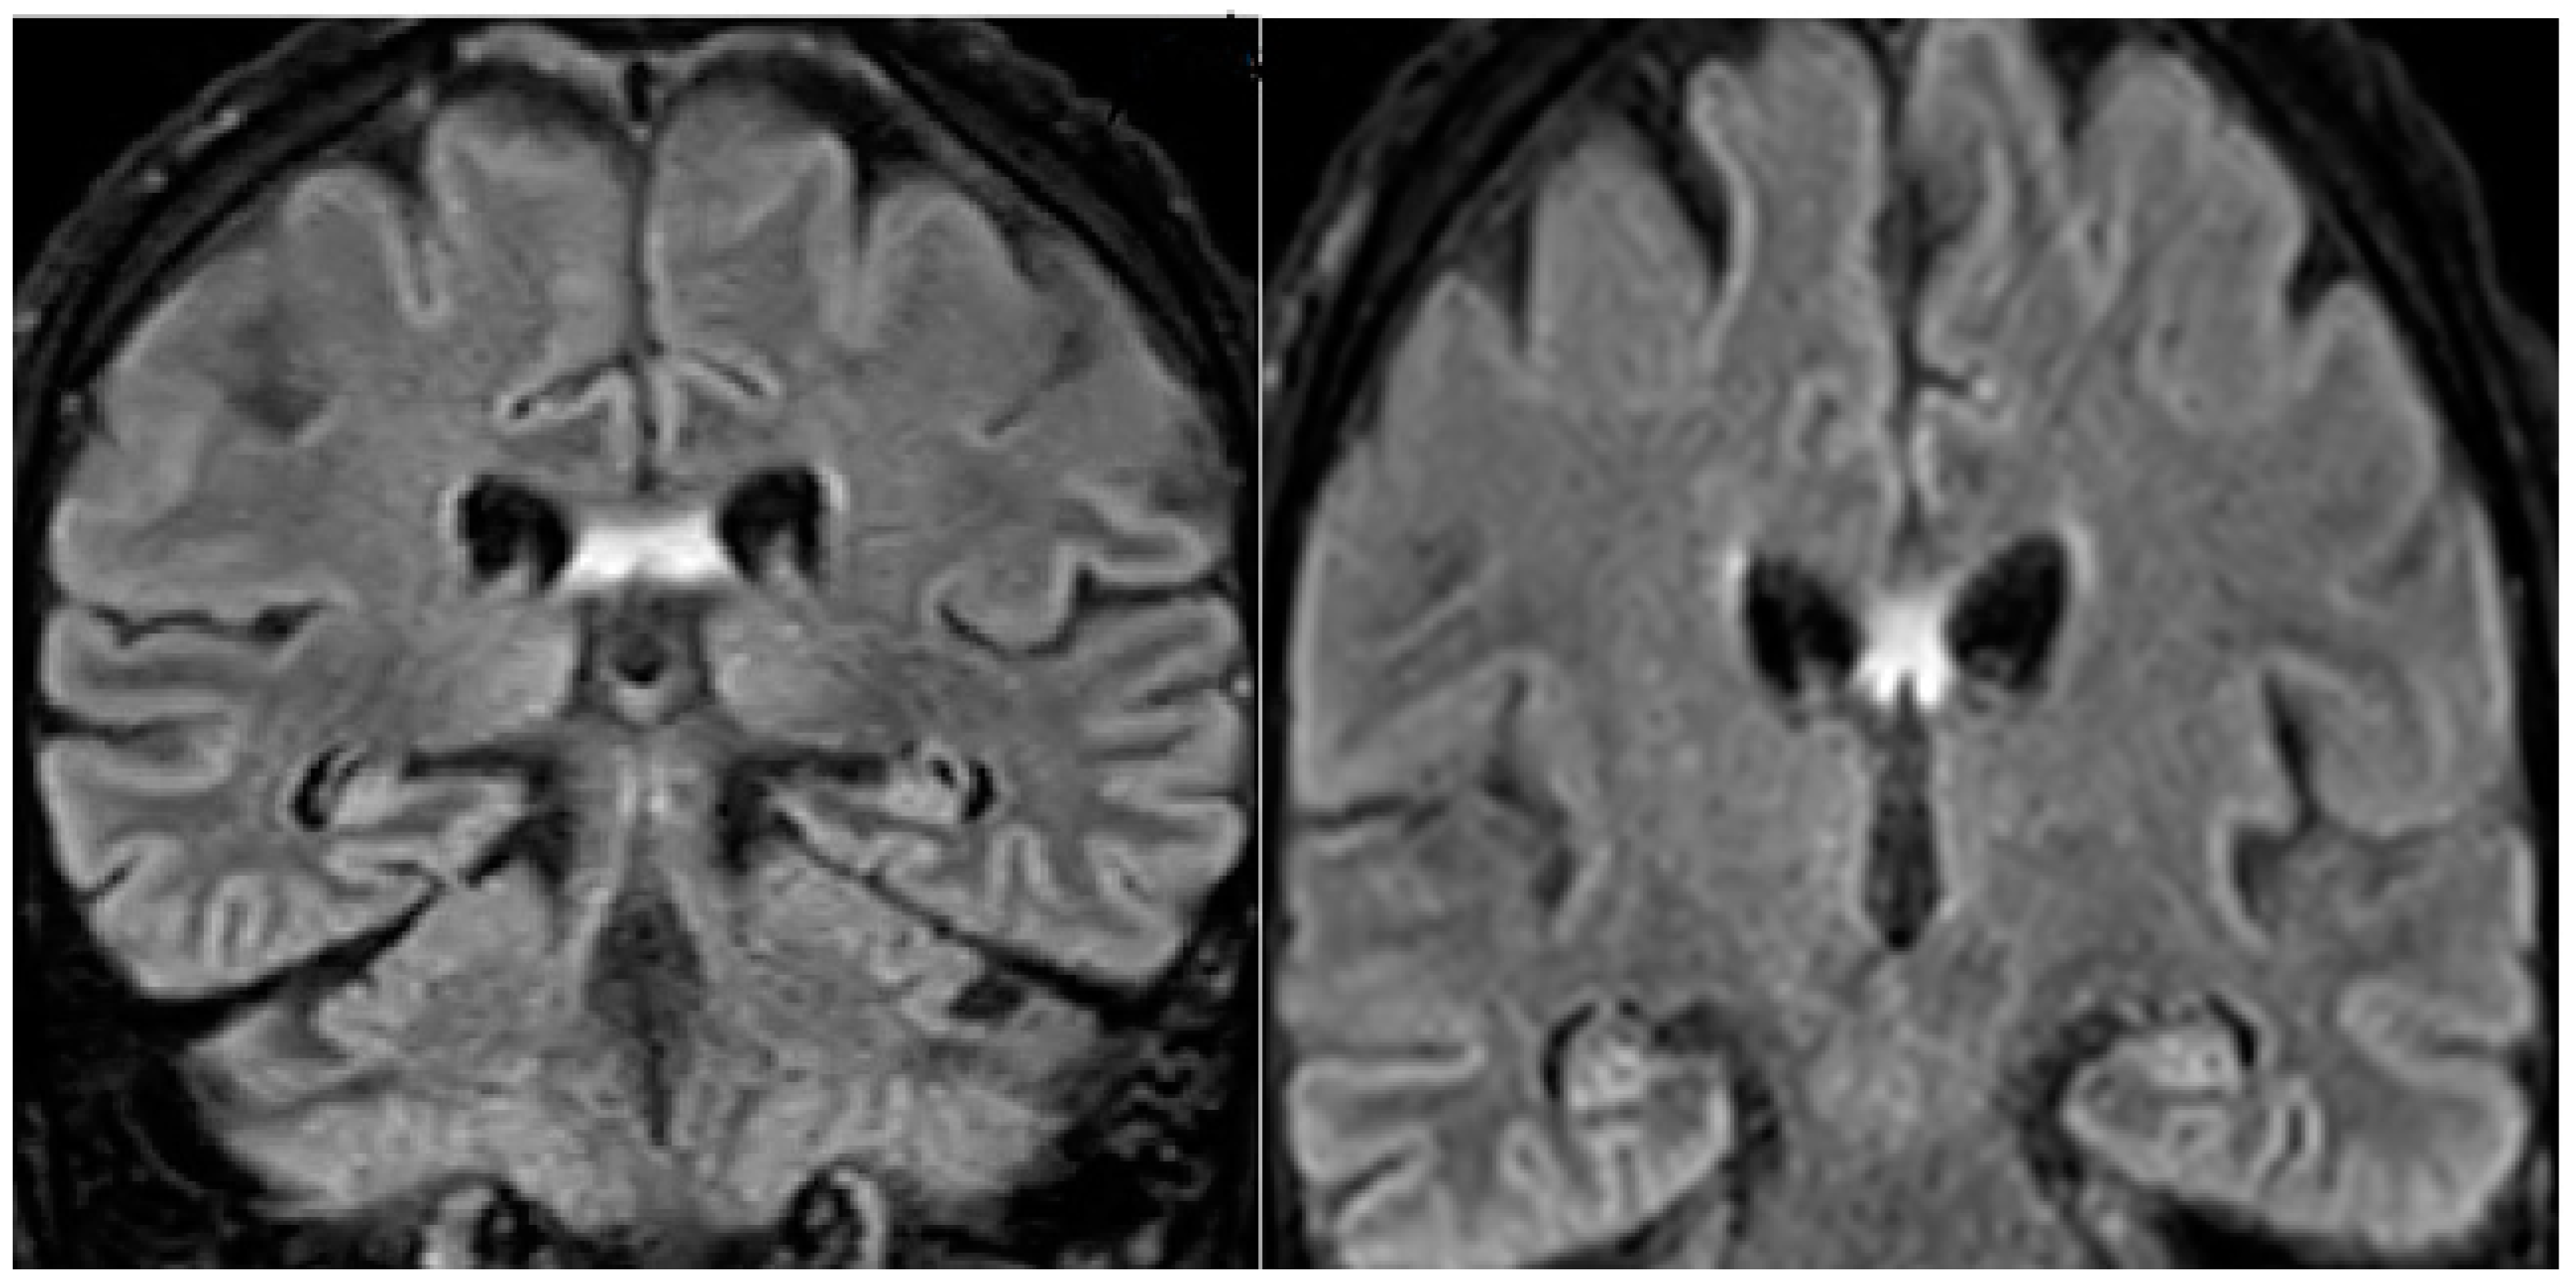

A 68-year-old man was referred to the neurologic department hospital of Piacenza (North Italy) in December 2023 with approximately a 3-month history of worsening gait, weakness, loss of appetite, and a confusional state. The patient was diagnosed with malignant melanoma in his left hand in April 2018. Primary melanomas of the third finger, last phalanx, and left hand were diagnosed, and the patient underwent amputation of the phalanx. A histological examination showed T4b stage IIC ulcerated melanoma. The mutation status was negative for the BRAF V600E mutation, and the patient underwent a complete staging with total body computerized tomography (CT) scans, which were negative for metastasis. The patient, 3 years later, developed lung and liver metastases, one metastasis of 2 cm in diameter at the left liver lobe and one metastasis at the superior left lung lobe of 1.5 cm in diameter. Treatment with pembrolizumab 200 mg every 3 weeks was then initiated on 15 July 2021. After six months of pembrolizumab, restaging with CT and FDG-PET/CT showed complete remission. The treatment was continued for 14 months and then stopped due to grade 3 diarrhea. The patient was in complete remission when, 10 months after the cessation of pembrolizumab therapy, he developed the following neurological symptoms: confusion, an altered mental state, progressive memory loss, and gait disturbance. The neurological examination did not display focal deficits. Cognitive testing revealed MMS 18/30. Head magnetic resonance imaging did not reveal brain metastasis, signs of carcinomatous meningitis or stroke, and evidenced hyperintensity in the fornix bilaterally on flair imaging (Figure 1).

Figure 1. Brain MRI of the patient showing bilateral fornix hyperintensity in the FLAIR (fluid-attenuated inversion recovery) sequences.